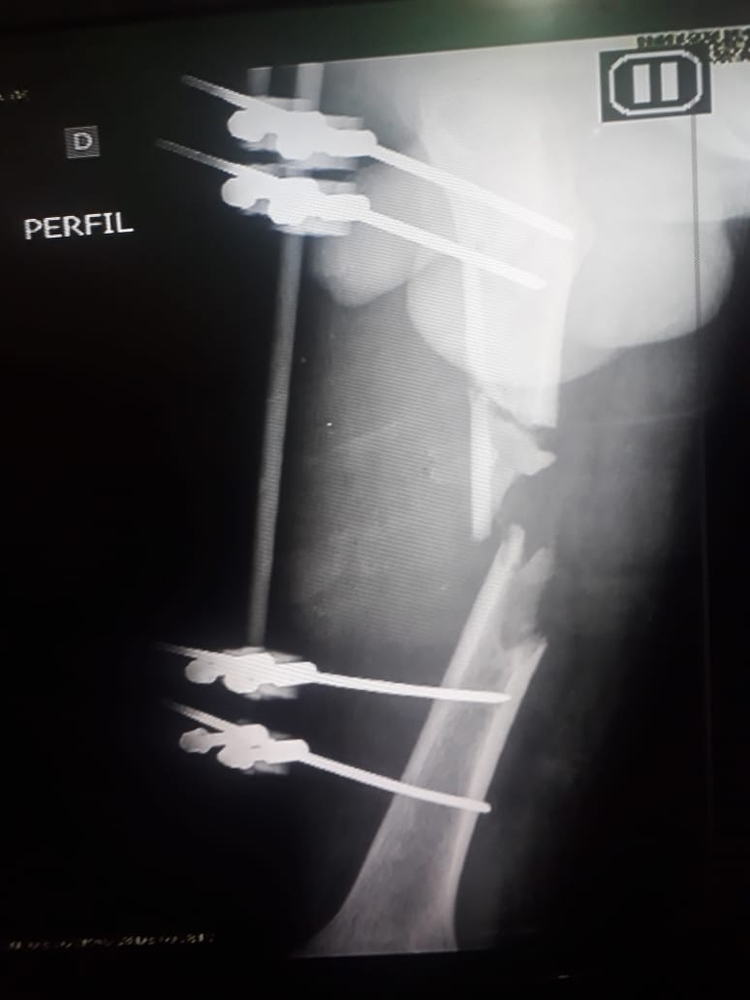

O acidente deixou fraturas no braço e no fêmur de Filipe. Apesar da sorte de ter sobrevivido sem maiores problemas, Filipe ainda não pode seguir a vida tranquilamente, pois o acidente o fez perder 7 centímetros de perna, e há um ano e 7 meses, ele aguarda por uma cirurgia no Hospital Adriano Jorge, que a todo esse tempo, alega falta de material.